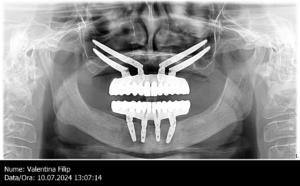

Doamna Filip a avut parte la clinica DentOP de cea mai complexă reabilitare orală, utilizând implanturi zigomatice.În urma unei consultații cu Dr. Cazacu Corrado, s-a constatat o retracție osoasă severă la nivelul maxilarului, făcând imposibilă utilizarea implanturilor convenționale pe termen lung. Radiografia atașată mai jos ilustrează situația clinică inițială.

Într-o singură intervenție chirurgicală, au fost inserate pacientei 4 implanturi zigomatice la maxilar, iar la mandibulă au fost extrasi dinții rămași și inserate 4 implanturi convenționale. Deși a fost cel mai complex caz de reabilitare orală, pacienta a declarat:„Când am ajuns acasă, mă așteptam să fie ceva dureros. În schimb, nu am simțit absolut nimic și m-am simțit foarte bine!”

Implanturile zigomatice sunt un tip special de implant dentar, conceput pentru pacienții cu pierdere severă de os maxilar. Aceste implanturi sunt mai lungi decât cele convenționale și sunt ancorate direct în osul zigomatic (osul pomeților), oferind o soluție stabilă și durabilă pentru fixarea protezelor dentare. Puteți vedea pe radiografia panoramică a pacientei cum arată implanturile zigomatice inserate.